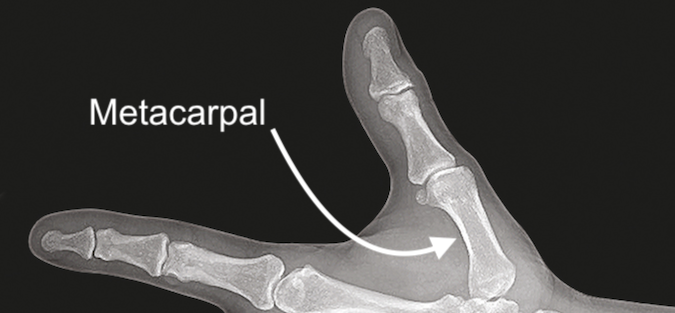

DescriptionBone that connects the thumb to the carpals at the base of the hand. Diagrams & Photos Thumb Metacarpal Bone Anatomic View Thumb Metacarpal Bone Diagrammatic View Thumb Metacarpal Bone X-ray View Anatomy References Anatomic Abbreviations Hand Surgery Resource Anatomy Diagnostic Guide (Chapter)